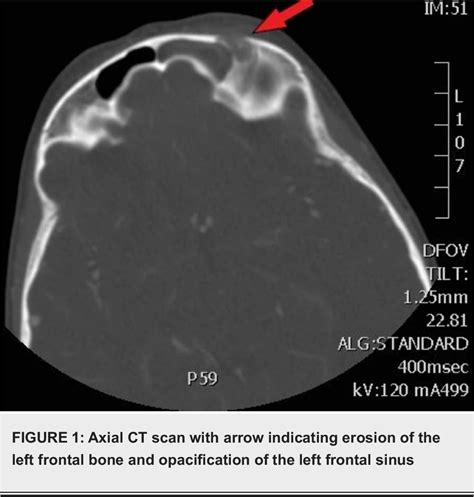

Diagnosis of Pott's Puffy Tumour relies heavily on advanced medical imaging. Physical examination is insufficient to determine the depth of the bone involvement or the presence of intracranial complications. Radiologists and surgeons work in tandem to evaluate the extent of the disease.

Computed Tomography (CT) To visualize bone erosion, sinus opacification, and subperiosteal abscess.

Magnetic Resonance Imaging (MRI) To detect intracranial complications, such as epidural abscess or venous sinus thrombosis.